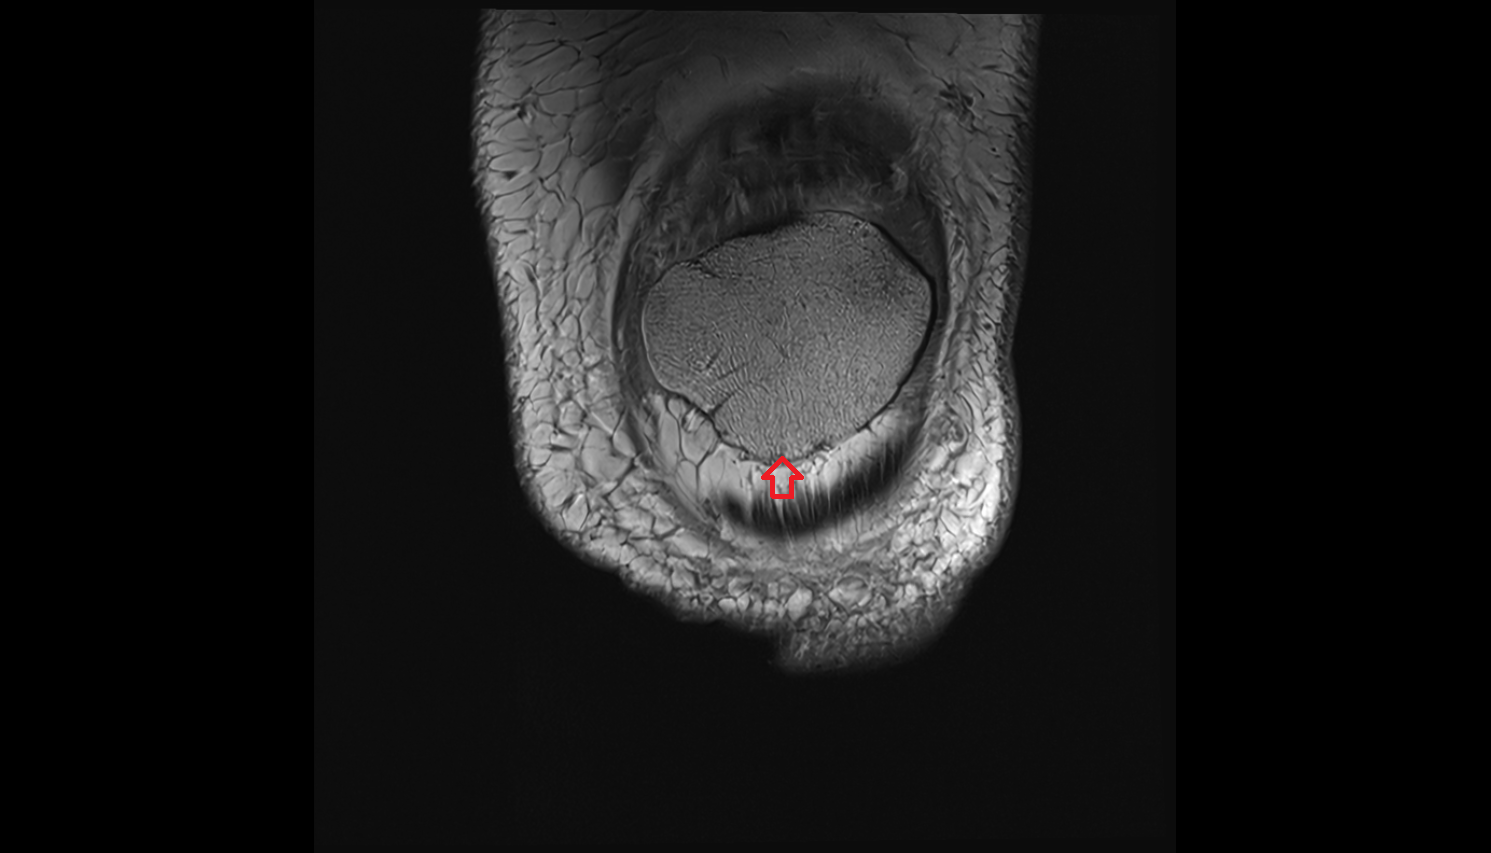

- Medial meniscus

- Lateral meniscus